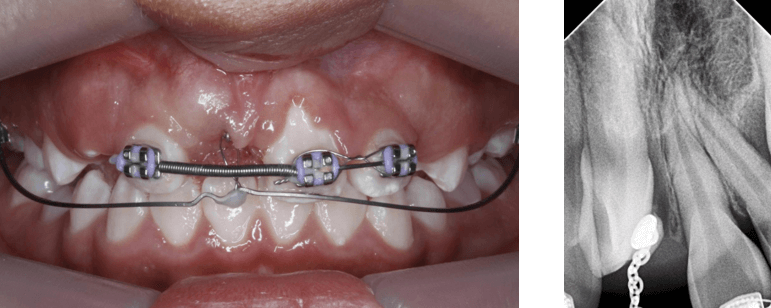

El plan de tratamiento consistió en retirar la ortodoncia fija anterior y cementar brackets con técnica 4x2 filosofía Roth 0,022 con una secuencia de arcos 0.014 niti termoactivado, 0.018niti termoactivado previo a procedimiento quirúrgico. Se requieren 8 mm (espacio requerido) para el incisivo central 1.1 y se tenía un espacio inicial de 6,09 (espacio disponible) (Fig 9 y 10), para control radiográfico inicial se realizó una radiografía periapical con técnica de bisectriz (Fig 11)

Fig 9 y 10. Espacio disponible y espacio requerido

Fig 11. Rx periapical con técnica de bisectriz

En el siguiente mes se utilizó la técnica de tracción con arco segmentado, donde se utilizaron el arco 0.018 niti superior sujeto a los incisivos superiores 1.2, 2.2 y 2.1 junto con un resorte de espigas cerradas para mantener el espacio entre el 1.2 y 2.1 y el arco de TMA 17 x 25 colocado en los tubos 16 y 26 respectivamente. Se realiza la activación con 100 gramos de fuerza. (Fig 17)

Fig 17. Fotografía de arco segmentado 0.018 para tracción de incisivo central 1.1